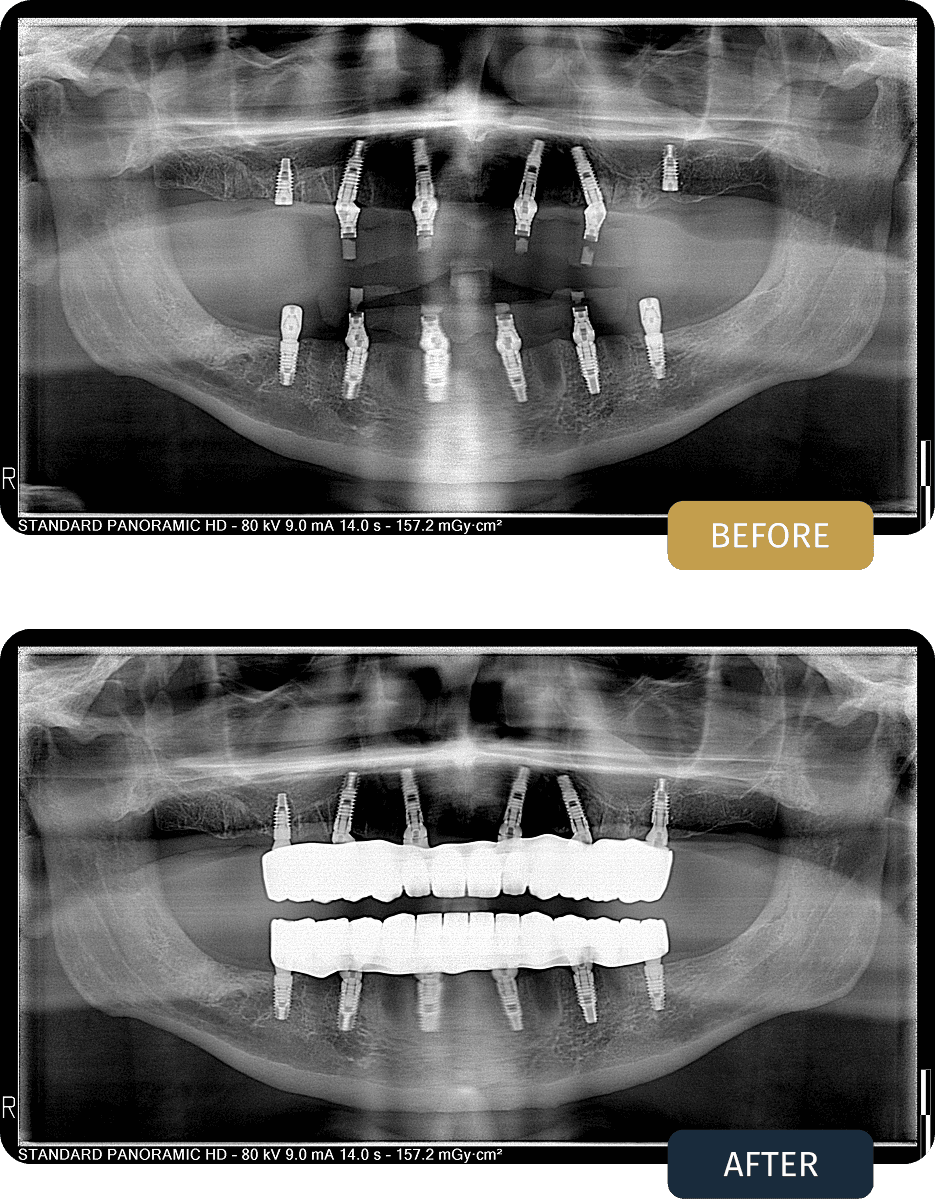

BEFORE

Andrew initially presented with advanced tooth loss in both jaws, resulting in reduced chewing function, poor stability, and compromised quality of life.

Following extractions and implant placement during his first stage of treatment, a healing period was required to allow full osseointegration before proceeding to definitive prosthetic restoration.

The panoramic X ray shown represents Andrew’s second visit, taken after the healing phase, confirming that the implants had successfully integrated and were ready for final prosthetic loading.

AFTER

Post treatment panoramic imaging confirmed stable, well integrated implants in both jaws with correctly seated titanium bar supported restorations.

The final prostheses delivered a fixed, balanced bite with excellent stability, restoring full chewing function and long term comfort.